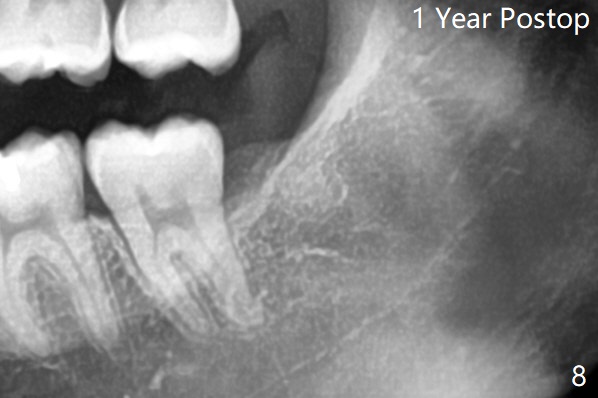

Osteogen plug was placed in #17 socket 1 year ago.

Buccal Impaction Last Next